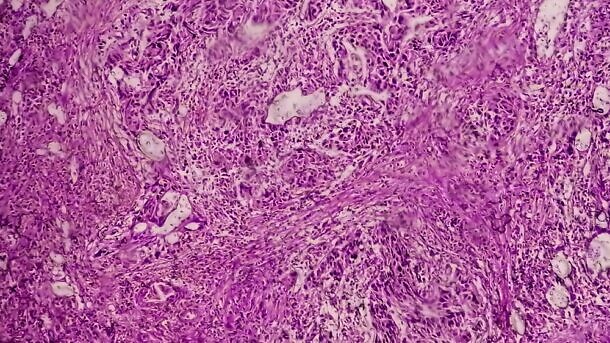

סקיטוזומאב גוביטקאן (SG) נמצאת בשימוש נרחב כטיפול בסרטן השד ובקרצינומה של תאי המעבר (urothelial carcinoma), אך זמינות המידע בנוגע ל- AEs של הטיפול עודנה מוגבלת.

במחקר שממצאיו פורסמו בכתב-העת ‘Clinical Pharmacology & Therapeutics’ החוקרים בדקו את ה-AE בעקבות הטיפול עם SG באמצעות כריית מידע ממסד הנתונים של ה- FDA adverse event reporting system (FAERS). החוקרים העריכו את הקשר בין הטיפול עם SG לבין תופעות הלוואי (AEs) באמצעות ה- information component (IC). בנוסף, החוקרים ערכו אנליזה רגרסיה לוגיסטית מרובת משתנים עבור כל האותות (signals) שאותרו על מנת לבדוק את גורמי הסיכון הנקשרים עם תופעות לוואי המובילות לאשפוז.